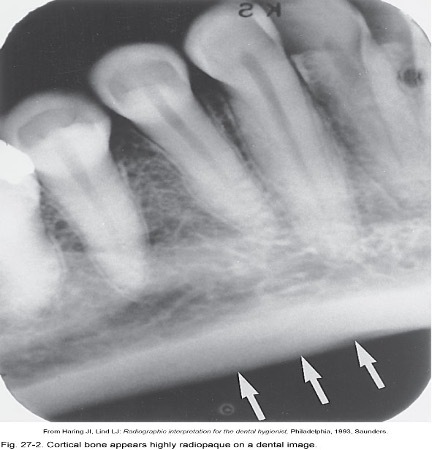

8

Q

How does cortical bone appear on x-ray

A

radiopaque

What is this a picture of?

Cortical (Compact Bone)